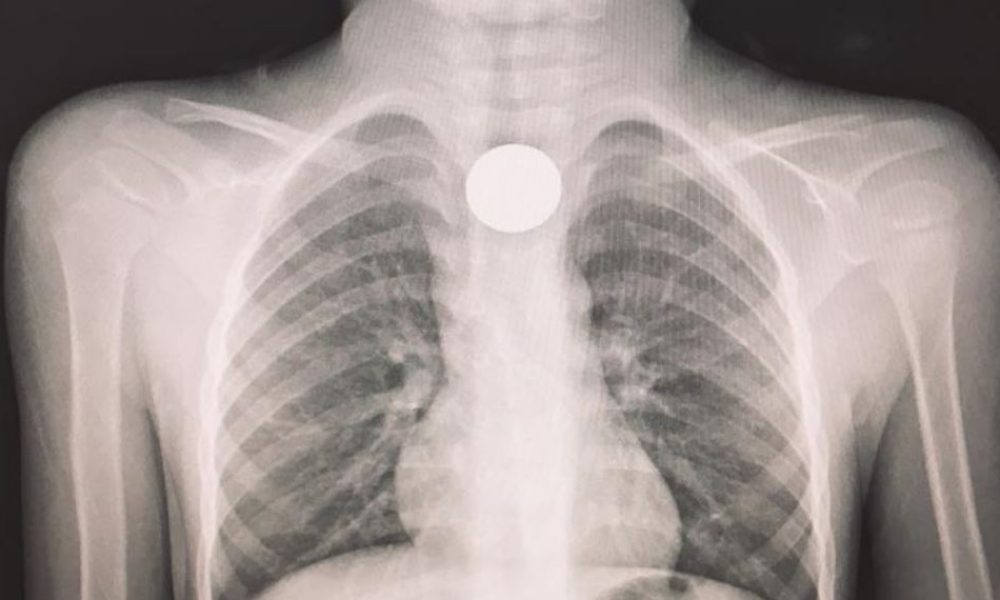

Giunto al pronto soccorso dopo aver ingoiato una moneta, viene trasferito in elicottero all’ospedale di Cosenza dove, dopo un tempestivo intervento, è stato dichiarato fuori pericolo.

“Si è conclusa positivamente la disavventura del piccolo A. M., 4 anni, italiano con genitori stranieri, che in mattinata era stato accompagnato al pronto soccorso dello Jazzolino. A dire dei familiari, il bimbo mentre giocava aveva probabilmente ingerito un corpo estraneo, poiché improvvisamente aveva smesso di parlare e si portava angosciosamente le mani alla gola.”